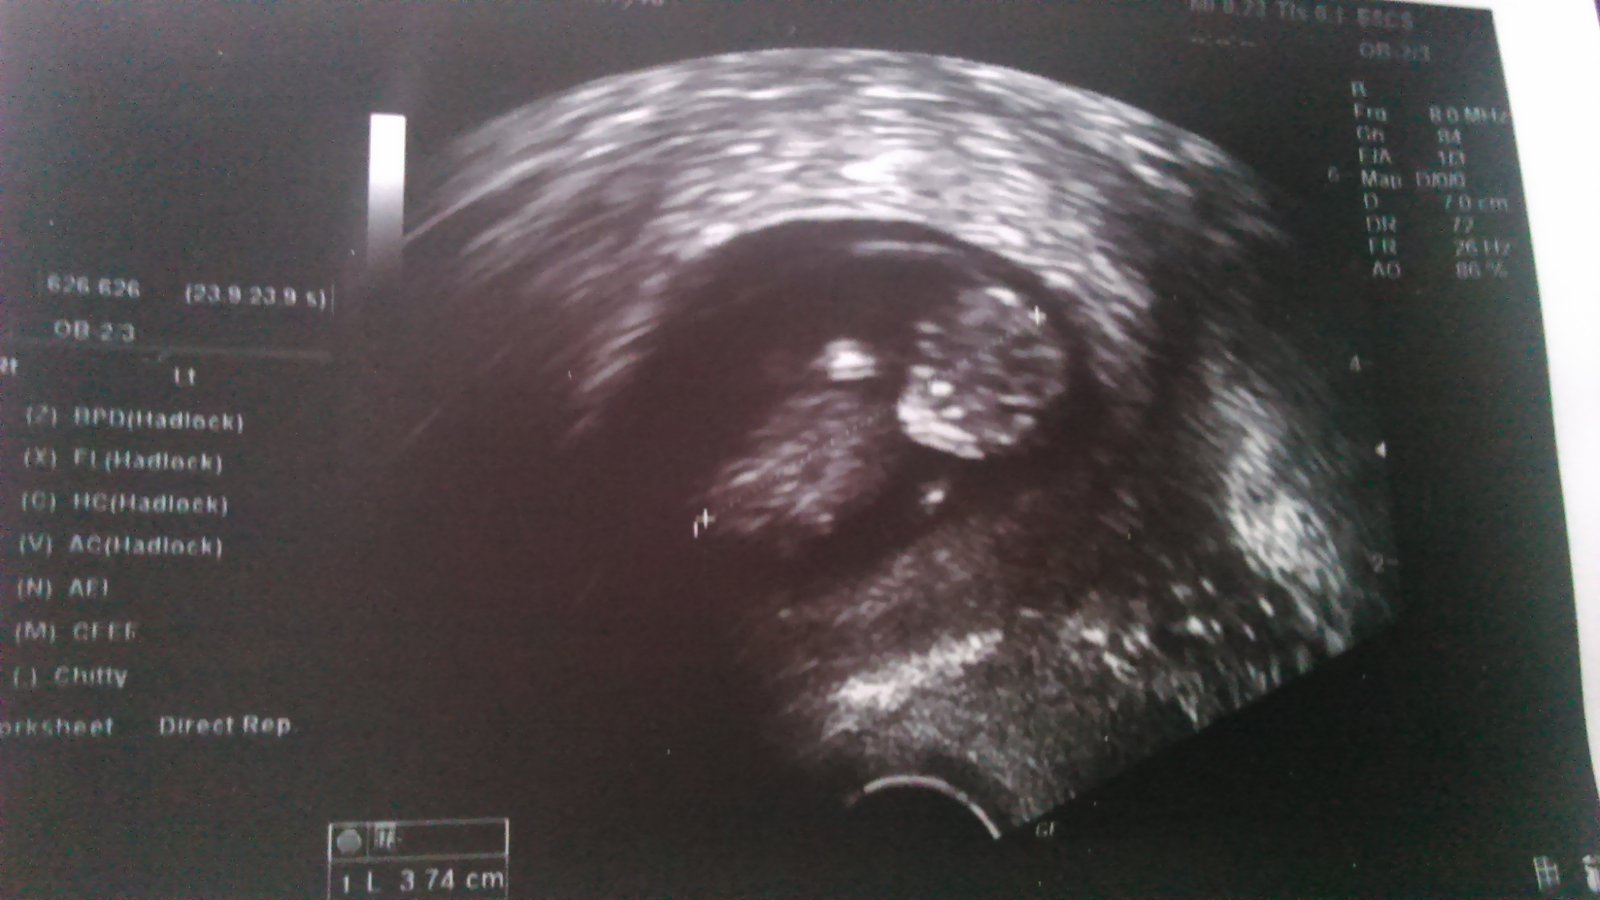

@kakatulik no ako ten cas leti 🙂 akurat mi robili testy na vyvojove vady vsetko je v poriadku tak sa tesime 🙂 minuly stvrtok som bola na kontrole sestricka ma vazila a ani gram len brucho rastie 😀 nevolnosti uz nastastie presli a citim sa fajn. Zajtra si mam dat posledny Duphaston, tak hadam sa nic nestane. Aha nasa nadhera 🙂